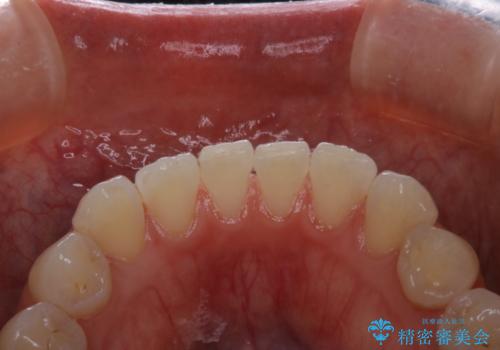

- 専門的な機械ででしっかりとキレイにクリーニングしてほしいとのことでしたPMTC60分コースを行いました。

PMTCは、歯に付着した汚れを除去していくため、着色が気になる場合にも行うことができます。ご自身でのセルフケアだけで着色を落とそうとすると、逆に歯を傷つけてしまったり、精密に汚れを除去できないこともあります。また、日常生活で着色しやすい飲食物を避けたりすることはストレスに感じてしまったり、あまり現実的ではありません。

毎日丁寧に歯磨きをしていても、日常生活での飲食物などにより着色してしまうことはあります。PMTCでは、歯の表面の凸凹にミネラルを補給して、ツルツルの表面に仕上げます